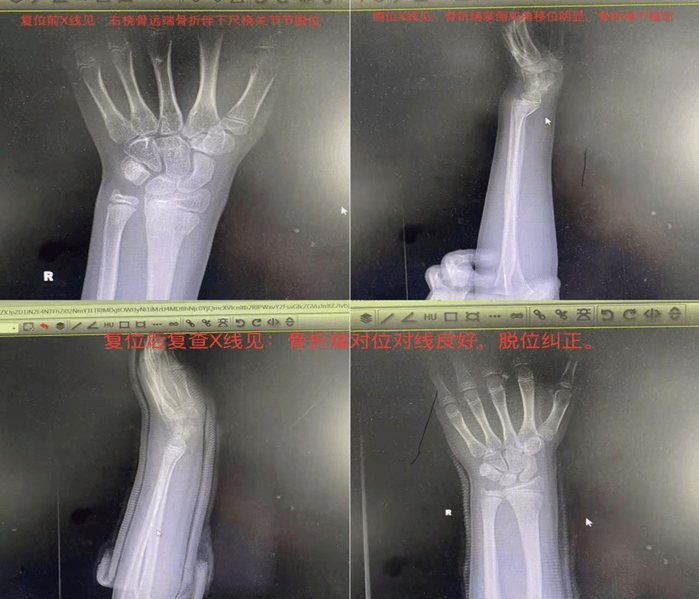

患者张某某,6岁,摔伤致右腕部剧痛、活动受限。X线检查确诊为“盖氏骨折”。当日即行手法复位+石膏固定术,过程顺利。术后复查显示骨折端解剖对位,关节脱位完全纠正。后续随访可见骨折愈合良好,手腕功能恢复正常。